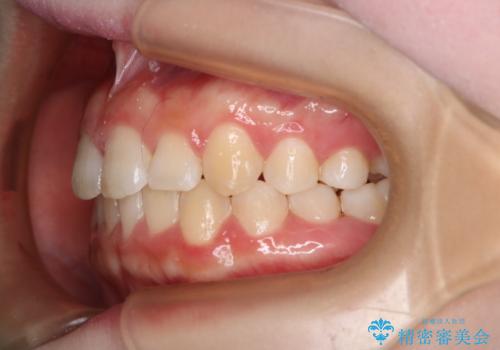

- 前歯のガタつきの改善を主訴に来院された患者様です。

ガタつきによる上顎正中の空隙や歯の突出感も気にされていました。

費用を抑えたいとの事だったので歯の移動量なども考慮し、インビザライン・ライトパッケージでの治療を計画しました。